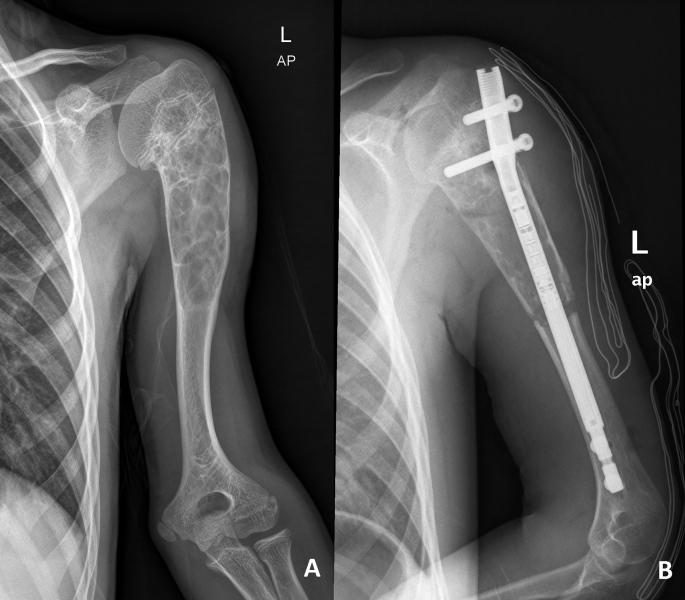

We report the treatment process of a pediatric patient with deformity and shortening in the arm after a recurrent aggressive aneurysmal bone cyst (ABC) in the proximal humerus. The patient was treated with curettage of the lesion and lengthening on an intramedullary nail following an osteotomy just distal to the ABC. The period of lengthening was approximately 50 days. At the end of the treatment the lengthening goal was achieved without any neurovascular complication. There was a minimal loss in shoulder hyperabduction due to the deformity of the humeral head.

我们报告了一名肱骨近端复发性侵袭性骨囊肿(ABC)后出现手臂畸形和缩短的儿科患者的治疗过程。患者接受了病变刮除术,并在ABC远端进行截骨后,使用髓内钉延长。延长时间约为50天。治疗结束时,达到了延长目标,且未出现任何神经血管并发症。由于肱骨头畸形,肩关节外展功能仅有轻微丧失。